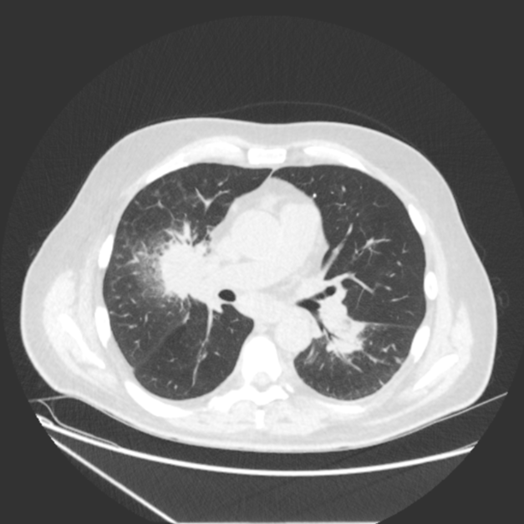

Pulmonary Nodules on CT

A chest CT scan is a critical tool in the assessment of pulmonary nodules. Based on the British Thoracic Society guidelines, this package includes concise educational materials explaining the assessment of lung nodules, as well as real-world training cases to develop your CT interpretation skills.